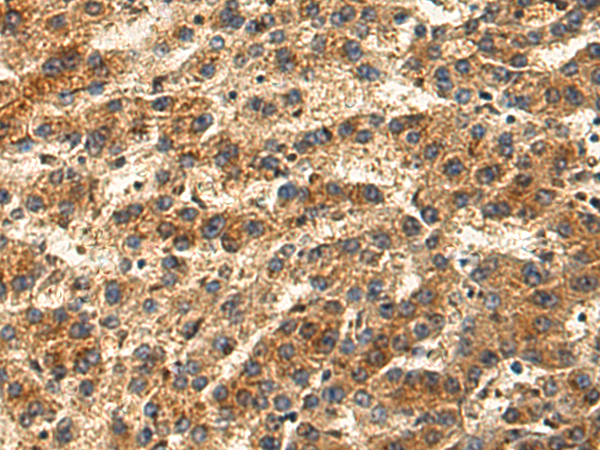

分类: 科研抗体货号: P03353别名:应用: IHC反应种属: Human, Mouse